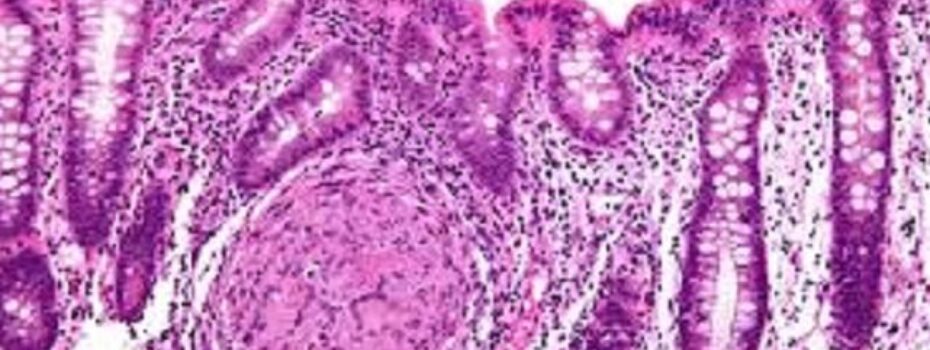

Sono piuttosto frequenti ma sottostimate: stiamo parlando delle malattie infiammatorie croniche intestinali (MICI), un gruppo di patologie croniche a carattere reattivo che interessano il canale digerente. Oggi, con i dottori  Natalino Carmelo Pennisi  medico-chirurgo specialista in Radiodiagnostica, e  Michelle (k/a Mikhaila) Muscat  medico-chirurgo specialista in Patologia Chimica,  andremo ad occuparci delle due più comuni: la […]